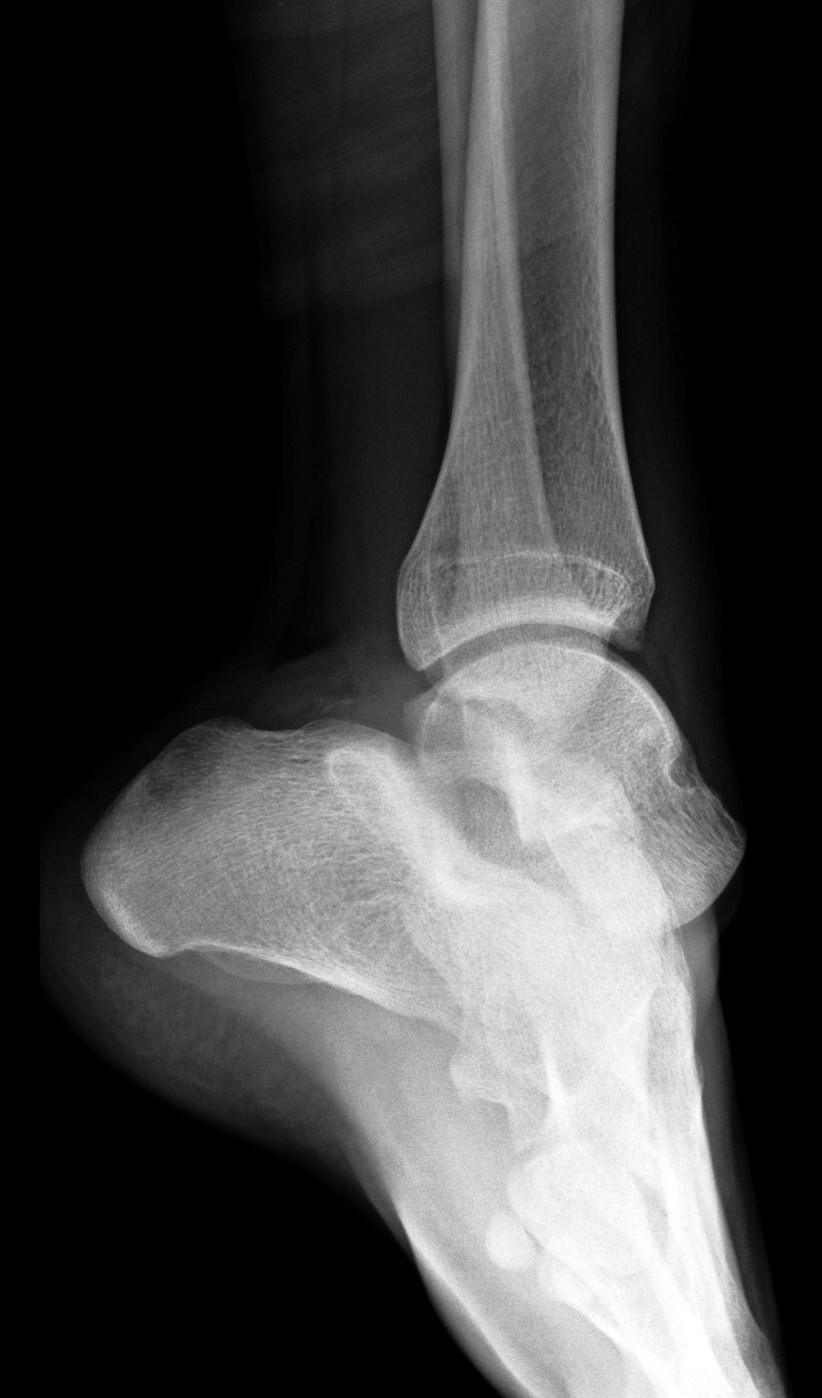

16 y/o s/p skateboard injury. Severe pain.

Medial subtalar dislocation. The photo is a representation, not this actual patient. 80% are medial like this. Trauma to an inverted plantar flexed ankle. Reference article.

Medial subtalar joint dislocation( RID3029 )